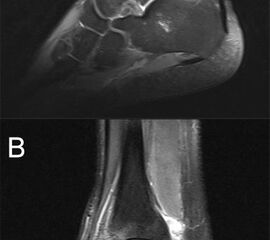

Die Magnetresonanztomographie (MRT) hat gezeigt, dass Knochenprellungen („bone bruises“), Knorpelschäden und andere Weichteil-Verletzungen erkannt werden 13 und mit arthroskopischen Befunden korrelieren 14.

Obwohl die MRT mittlerweile als Goldstandard für die Beurteilung von OCLs gilt sollte bedacht werden, dass aufgrund der hohen Sensitivität der Methode die Signalmuster im Sprunggelenk die Schwere der Knochenverletzung überschätzen können. Zudem wurde die gleiche diagnostische Genauigkeit für CT und MRT festgestellt 15.